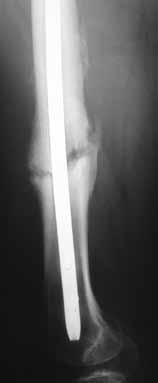

-Figures 10a and 10b are the radiographs of a 33-year-old man who was involved in a high-speed motorcycle crash. He sustained an isolated injury to the right lower extremity. On the day of injury, he was treated with open reduction and internal fixation of the femoral neck and retrograde nailing of the femur.

Radiographs are shown in Figures 10c through 10f. Alternative treatment with a cephalomedullary device alone would be more likely to lead to which of the following outcomes?